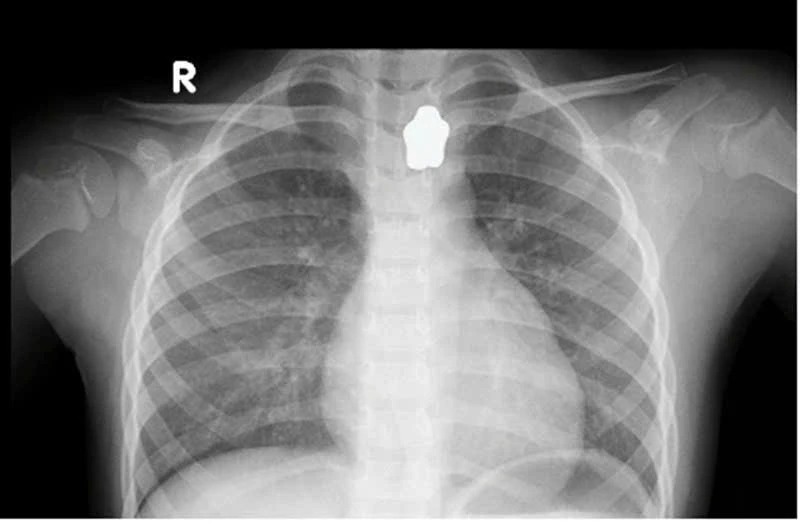

Bệnh nhi N.N.N.Y (ngụ TP Thủ Đức) nhập viện trong tình trạng mắc nghẹn, đau vùng cổ, khó thở nhẹ. Kết quả chụp X-quang ghi nhận, dị vật hình ngôi sao cản quang mắc tại vùng cổ.

Đối với trường hợp bệnh nhi Y., vị trí mắc tại thực quản trên, bề mặt trơn láng. Các bác sĩ tiến hành dùng kềm cá sấu gắp dị vật nhưng thủ thuật thất bại.